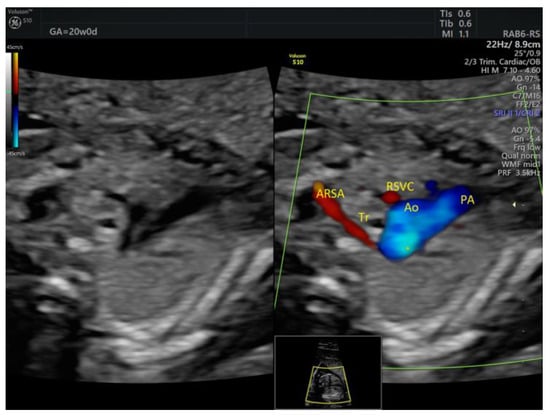

| Isolated ARSA | 6 | - | - | 3VT color | - | 0 | 6 | 0 | 2/5 |